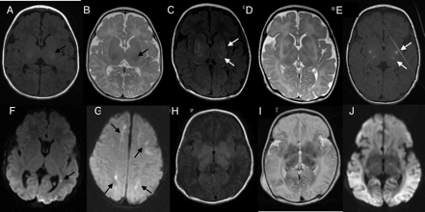

Calcificações intracranianas neonatais e diagnóstico diferencial com infecções congênitas (pseudo-TORCH)